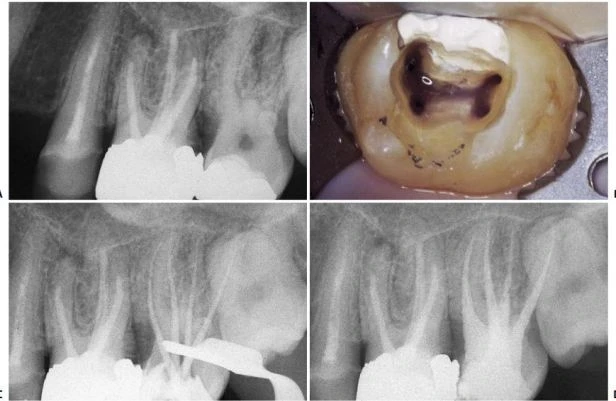

Về mặt giải phẫu học, răng cối nhỏ thứ nhất trên có thể có hình dạng hoàn toàn khác. Ống tủy cong hình lưỡi lê ở 1/3 chóp chân răng là một dạng điển hình. Hiếm khi tìm thấy một ống tủy đơn, hình elip trong một chân răng; thường gặp hai ống tủy giao nhau ở 1/3 giữa với hai lỗ chóp trong một chân răng (38%) hoặc hai ống tủy (thường cùng chiều dài) ở trong hai chân răng riêng biệt (60%). Hiếm hơn nữa có thể thấy ba chân răng với ba ống tủy và những lỗ chóp riêng biệt, chiếm 6% theo Carns và Skidmore , và 5% theo những tác giả khác. Trong những trường hợp này, RCN có hình dạng như răng cối lớn. Một ống tủy rộng hơn ở phía trong và hai ống nhỏ hơn ở phía ngoài, một ở phía gần và một ở phía xa (hình 11.46). Điều trị nội nha tốt hay không phụ thuộc vào việc tạo xoang tủy có đúng hay không: răng cối nhỏ trên với ba ống tủy thì cần tạo một xoang tủy có hình dạng chữ “T” với sự mở rộng theo chiều gần xa ở phần ngoài của xoang truyền thống. Sự thay đổi này cho phép tạo một đường vào tốt cho cả hai ống tủy ngoài. Nếu ba chân răng phân kỳ, ta có thể thấy được trên phim X-quang trước điều trị. Nếu ba chân răng chụm hoặc chồng lên nhau (hình 11.47A), ta có thể biết được trong lúc điều trị. Nha sĩ có thể nghi ngờ có hai ống tủy ngoài không chỉ nhờ vào sự hiện diện của 2 miệng ống tủy (thường không nhận ra hai miệng ống tủy riêng biệt), mà còn nhờ vào hướng của cây trâm thăm dò khi nó đi vào một trong hai ống tủy, hoặc hình dung trên phim X-quang thấy hình ảnh dị dạng nhưng những đường nét chung của chân răng vẫn bình thường [ví dụ: hoàn toàn nằm về phía gần (hình11.47 B)], ta có thể nghi ngờ còn một ống tủy ngoài thứ hai nữa mà hướng của nó nằm về phía xa hơn so với ống thứ nhất (hình 11.47 C, D).

Hình 11.47. A. Phim trước điều trị răng #14: Chân răng chồng lên nhau, không dễ nhận ra ba ống tủy. B. Dụng cụ đầu tiên được đừa vào miệng ống tủy (dường như là ống ngoài), hình ảnh dụng cụ đi theo một hướng bất thường so với hình ảnh chân răng. Nhìn kỹ thấy nó chuyển hướng về phía gần: dụng cụ đã đi vào ống gần ngoài. C. Uốn cong dụng cụ về phía xa rồi đưa vào cùng miệng ống tủy này, nó tự động đi vào ống xa ngoài. D. 34 tháng sau, phim X-quang cho thấy sự hiện diện của ba ống tủy.

Nếu có sự chia chân phía mặt ngoài- do đó hiển nhiên là có sự hiện diện của hai ống tuỷ mà nhà lâm sàng không chẩn đoán được- thì có thể dẫn đến làm thủng chân răng khi sửa soạn chân răng để đặt chốt hay khi quay cement để gắn chốt (mà nhà lâm sàng cứ nghĩ rằng chỉ có một ống ngoài mà thôi!) (hình 11.48). Vì những lý do trên, nên luôn có quyết định tối ưu số lượng ống tủy cần điều trị, thậm chí nếu chỉ để tự trù thời gian cần cho việc điều trị.

Hình 11.48. Không chẩn đoán thấy sự chia chân và kết quả là làm thủng thành. A. Phim trước điều trị. B. Lật vạt và nhận thấy sự thủng thành. C. Chuẩn bị xoang để hàn chỗ thủng. D. Trám xoang bằng Super EBA. E. Phim sau điều trị. F. Sau hai năm. G. Hình ảnh lâm sàng sau hai năm.

Trong phục hình răng cối nhỏ, có thể gặp khó khăn trong quyết định ống tủy tìm được là ống trong hay ống ngoài. Tìm ống tủy còn lại sai hướng rất nguy hiểm và có thể dẫn đến thủng thành. Trong những trường hợp này, việc chẩn đoán rất dễ nếu dựa trên X-quang chụp theo một hướng khác và ứng dụng qui tắc “phía ngoài” (buccal object rule).